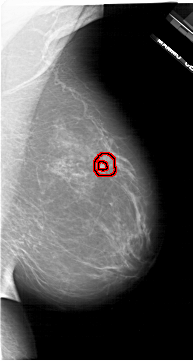

A_1620_1.RIGHT_CC

RIGHT_CC LINES 6271 PIXELS_PER_LINE 3661 BITS_PER_PIXEL 12 RESOLUTION 43.5 OVERLAY

FILE: A_1620_1.RIGHT_CC.OVERLAY

TOTAL_ABNORMALITIES 1

ABNORMALITY 1

LESION_TYPE MASS SHAPE IRREGULAR MARGINS SPICULATED

ASSESSMENT 5

SUBTLETY 3

PATHOLOGY MALIGNANT

TOTAL_OUTLINES 2

BOUNDARY

CORE